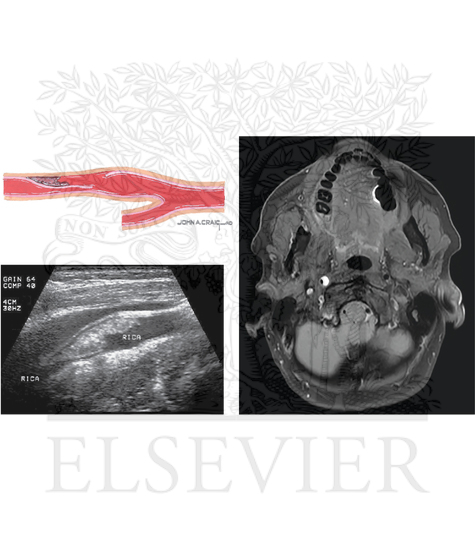

Arterial Dissection